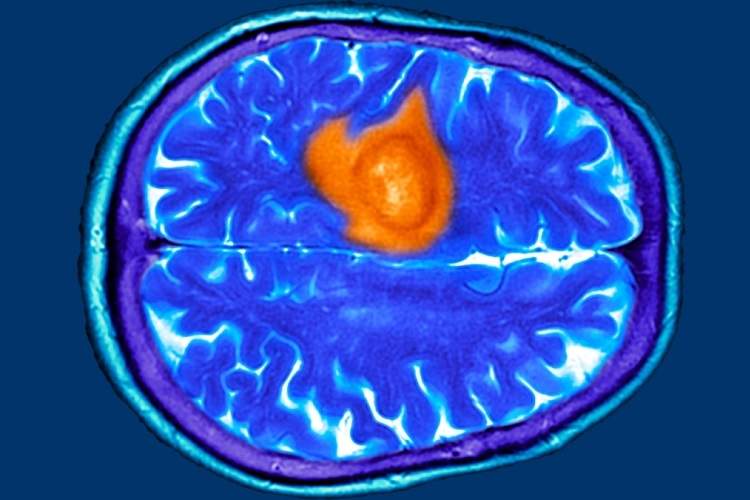

هفت نشانه پنهان تومور مغزی که ممکن است آنها را عادی بپندارید

تومور مغزی میتواند با علائمی مشابه بیماریهای رایج مانند اضطراب، عفونت سینوس یا یائسگی بروز کند. در پژوهشی که بر پایه مصاحبه با بیماران انجام شد، هفت علامت اصلی شایع اما فریبنده شناسایی شد. نخستین مورد، دشواری در یافتن کلمات است؛ برخی بیماران در صحبت کردن یا کامل کردن جمله دچار وقفه میشدند، موضوعی که ابتدا به استرس یا خستگی نسبت داده شد. دوم، مهذهنی یا Brain Fog است که با ناتوانی در تمرکز و فراموشی همراه میشود. اگر این حالت با مشکلات گفتاری یا بینایی همراه شود، نیاز به بررسی پزشکی دارد.